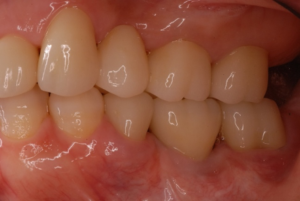

*この患者さんは奥から2番目をインプラント治療しています